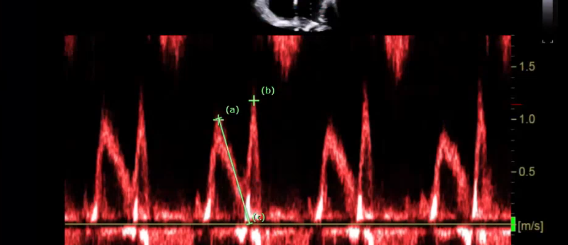

what single is this measurement for what are you going to peak, why would this doppler be important

this measure is for the pulmonary vein

Pulmonary vein peak systolic velocity (peak the S wave)

Peak D wave

peak the velocity of the atrial reversal or atrial duration

This will important when interrogate for MR, If the S wave is shorter than ourt D that is blunting so this coulf point to moderate or severe regurgitation if you see a reversal in these two